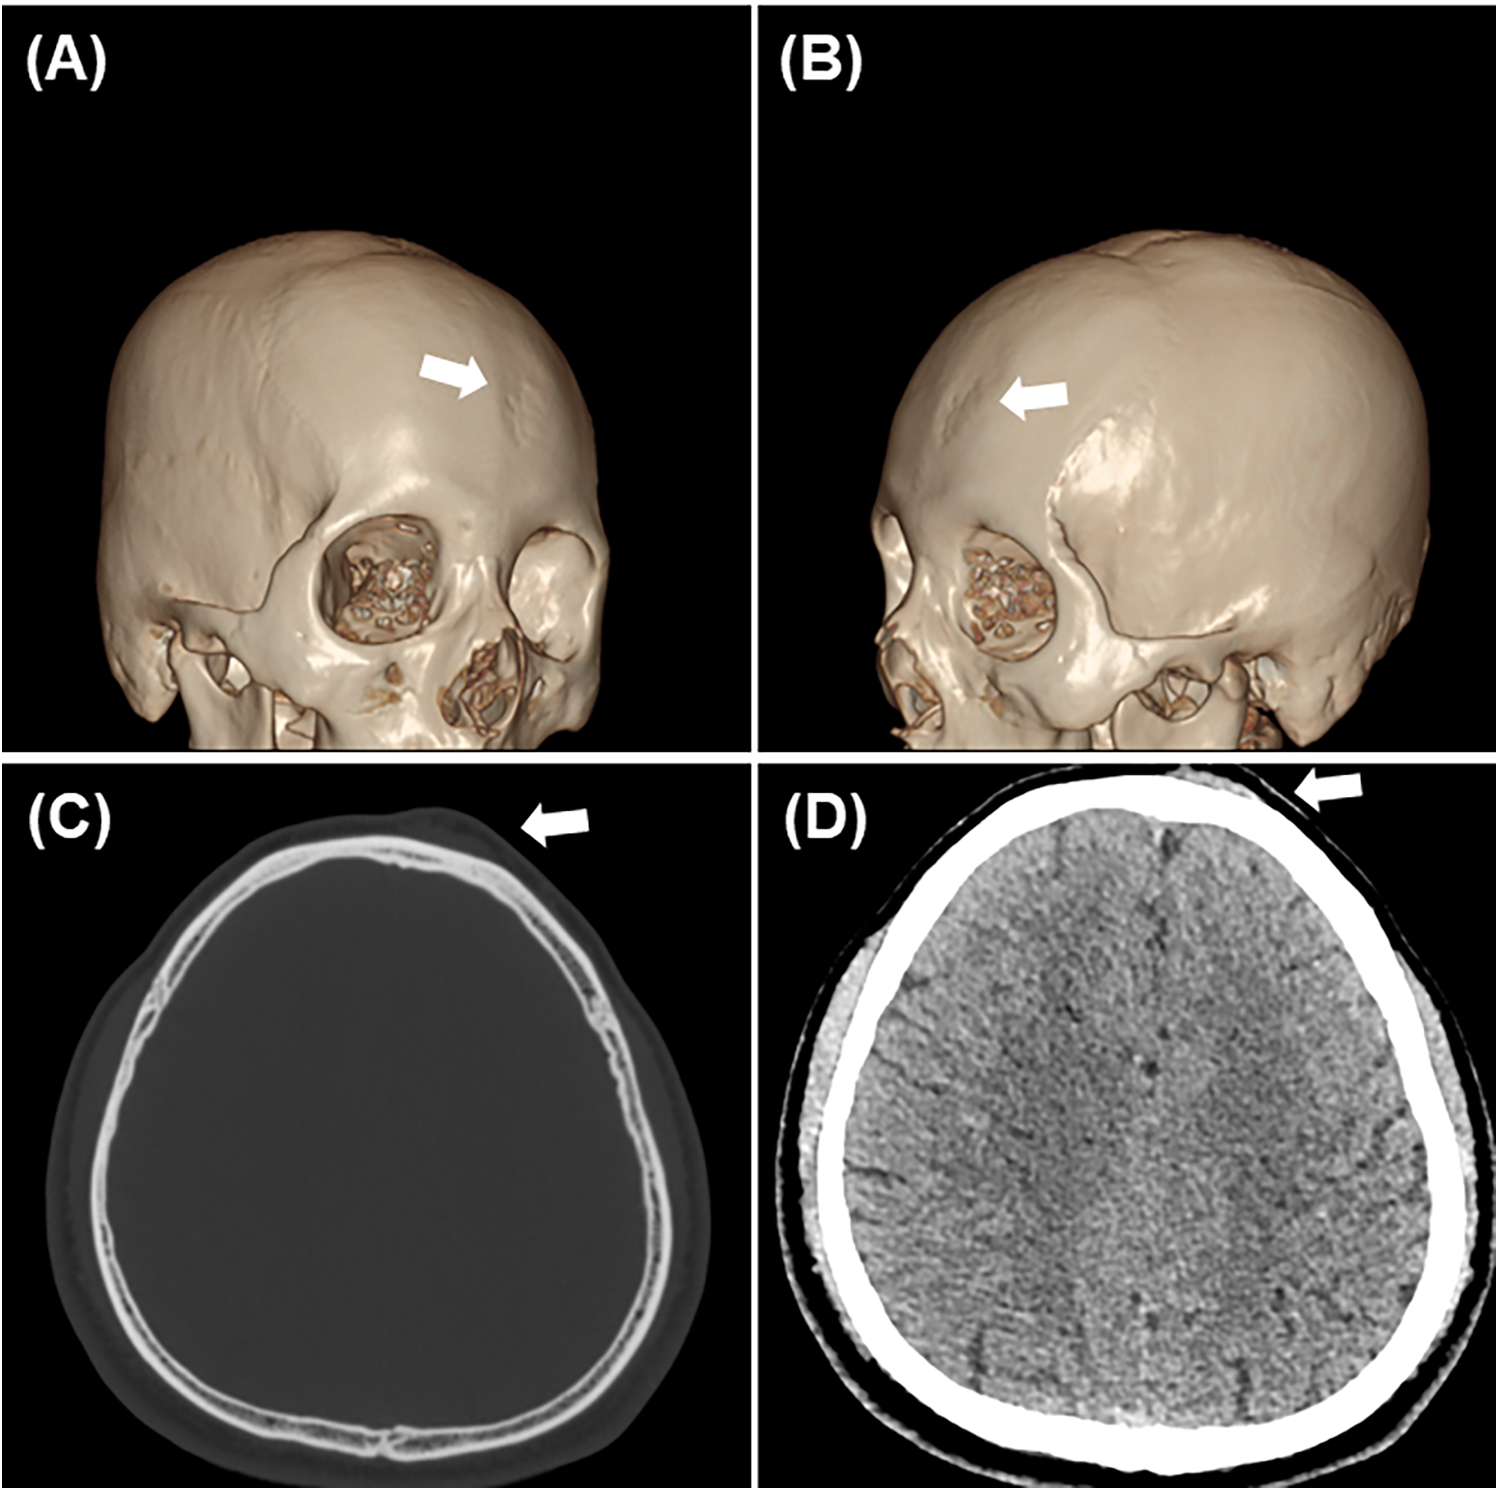

Three-dimensional Computed Tomography (CT) revealed a thin-walled region of the skull approximately 3 cm in diameter with several small holes and irregular, roughened bone, showing several small transosseous vessels extending through the surface of the skull (Figures 2A,B). Axial CT imaging further demonstrated localized bone thinning and a subcutaneous mass in the same region (Figures 2C,D). Based on these findings, a diagnosis of sinus pericranii was made. Angiography revealed no obvious thrombi, dural sinus abnormalities, or other vascular malformations, indicating that excision of the sinus pericranii was not affecting intracranial venous perfusion.

Figure 2. Imaging data. (A,B) Three-dimensional reconstruction indicated that the skull was rough and irregular, with numerous small holes on the surface (white arrow). (C,D) Axial imaging revealed localized bone thinning and a subcutaneous mass(white arrow).